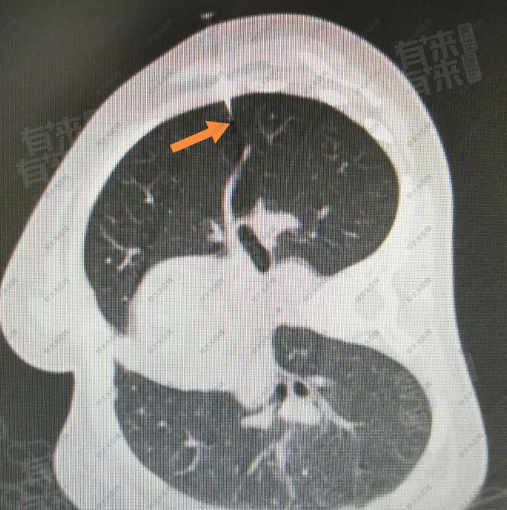

肺结节3-4mm,一般情况下不一定需要治疗。肺结节是指肺部影像上表现为直径小于或等于30mm的局灶性、类圆形、密度增高的实性或亚实性肺部阴影。对于3-4mm的肺结节,其性质通常难以确定,可能是良性的,也可能是恶性的早期表现。

- 如果是首次发现的3-4mm肺结节,医生通常会建议进行密切观察。这是因为这么小的结节,恶性的可能性相对较低。很多时候,这些结节可能是由于肺部的炎症、感染、陈旧性病变等引起的,随着时间的推移可能会自行消失或保持稳定。在观察期间,一般会要求患者在一定时间后(比如3个月、6个月或12个月)进行复查胸部CT,观察结节的大小、形态、密度等是否发生变化。

- 如果在观察过程中,肺结节没有明显变化,继续保持稳定,那么通常可以继续观察,无需特殊治疗。但如果结节出现增大、密度增高、形态改变等情况,就需要引起高度重视,进一步进行检查,如增强CT、PET-CT、支气管镜检查、经皮肺穿刺活检等,以明确结节的性质。